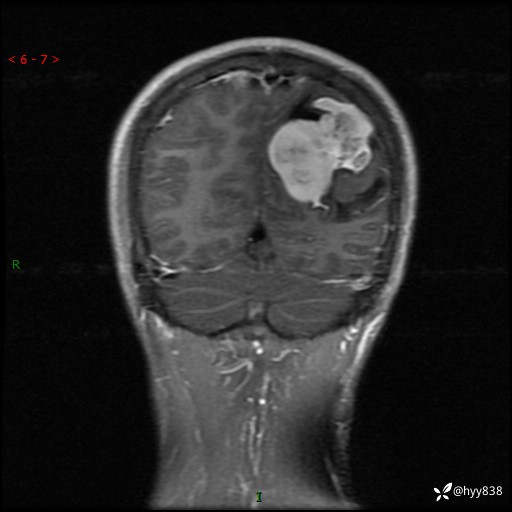

病例年轻小伙,头痛伴呕吐半年,渐进性加重1月。疑难病例,第一次见--结果公布~

性别:男

年龄:21岁

简要病史:头痛伴呕吐半年,渐进性加重1月

颅脑MRI平扫+增强